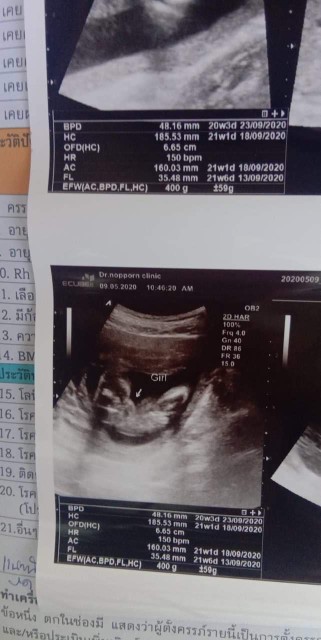

ใบอัลตร้าซาวด์

แม่ๆช่วยดูหน่อยคะ ผช.ใช่ไหมคะ หมอบอก ผช. บ้านไหนได้ ผช. ลงรูปใบซาวด์ให้ดูหน่อยคะ

ชายค่ะ

ผช. ค่ะ

ผ.ช ค่ะ

ผช. จ้า

ผช ค่ะ

ผช.จ้า

ผช.ค่ะ

ผชจ้า

ผช.คะ